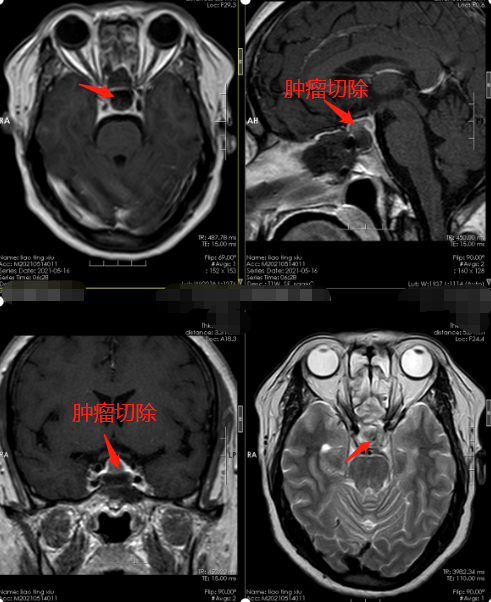

明确诊断后廖阿姨由内科转至神经外十科治疗,5月10号廖阿姨在全麻下行“神经内镜下经鼻蝶入路鞍区垂体瘤切除术”,术中磨除鞍底骨窗约1.5cm大小。钩刀“+”字型切开硬脑膜,见肿瘤灰白色,质硬,正常垂体组织位于右后方,予以保留,全切肿瘤,双侧海绵窦内侧壁无肿瘤残留,无明显脑脊液漏,术腔内留置明胶海绵片,检查无明显出血。术后安返监护室,给予止血、护胃、营养神经等对症和支持治疗。手术过程很顺利,肿瘤全切。

现在廖阿姨恢复很好,没有出现严重并发症,廖阿姨的家属很是感激,原以为是颈椎病,没想到竟是颅内良性肿瘤,廖阿姨的儿子说幸好来到了广东三九脑科医院,妈妈的病才能这么快的被及时诊断及治疗,非常感谢这里的医生和护士们。